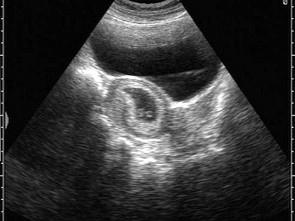

超声检查如图,孕囊内光环样结构为?(?)A.胚芽B.羊膜囊C.卵黄囊D.脐带E.胎儿

问题 超声检查如图,孕囊内光环样结构为?(?)

选项 A.胚芽 B.羊膜囊 C.卵黄囊 D.脐带 E.胎儿

答案 C